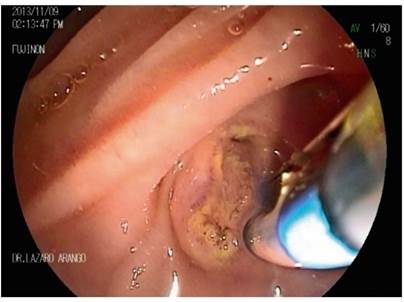

Primary pancreatic duct stones smaller than 5 mm are managed with standard ERCP maneuvers for stone removal (Figures 7, 8, 9, 10). Stones larger than 5 mm require the use electrohydraulic, extracorporeal, or Spyglass-guided electrohydraulic lithotripsy. In the latter case, the duct can be entered for use of a laser to fragment stones. 29 We have been gaining experience with the use of a cholangioscope which has been very useful for non-surgical management of patients with pancreatic stones. Figures 11, 12 and 13 show the Spyglass inside the Wirsung duct performing laser lithotripsy on a large stone. After the procedure, a pancreas stent is always placed.

Figure 9 Exploration of the Wirsung duct with Dormia basket (image courtesy of the Union of Surgeons SAS, Lázaro Arango).

Figure 10 Stone extraction from the Wirsung duct (image courtesy of the Union of Surgeons SAS, Lázaro Arango).